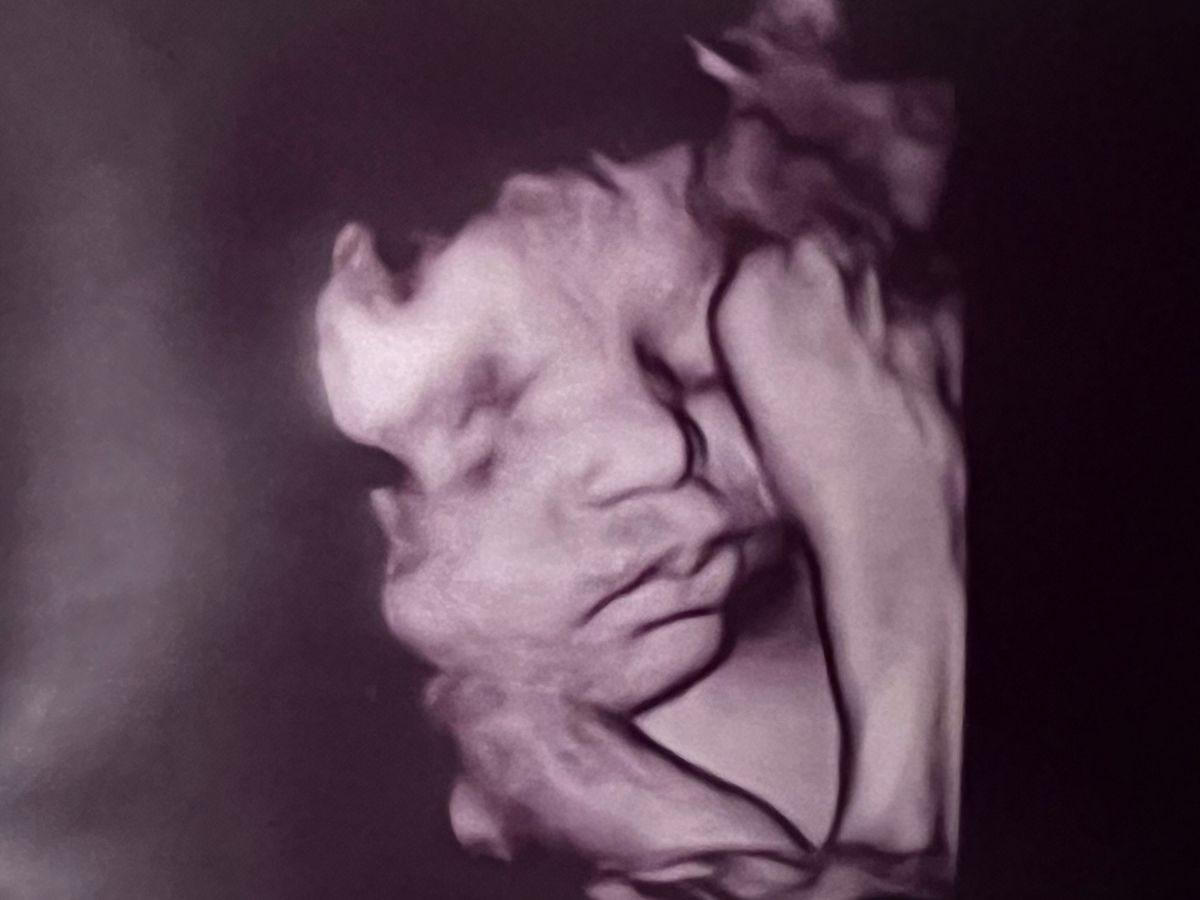

My name is Sam and I work with Jacey. Jacey and Mickey are welcoming a baby in September and as exciting as that can be, they were met with some hard news that their baby boy was diagnosed with HLHS, hypoplastic left heart syndrome. This requires 3 open heart surgeries, 2 of which will likely be before he is 6 months old. They will be temporarily relocating to Shands in Gainesville from Tallahassee. They are preparing to be hospital bound for a least a month and a half and will have extra expenses for housing and food on top of the medical bills to come. If we can help support Jacey and Mickey financially feel supported, it will help them concentrate on family and bring their precious home. As any parent can imagine, this is a scary time for Jacey Mickey and Cooper. Let’s gather together to support their family.